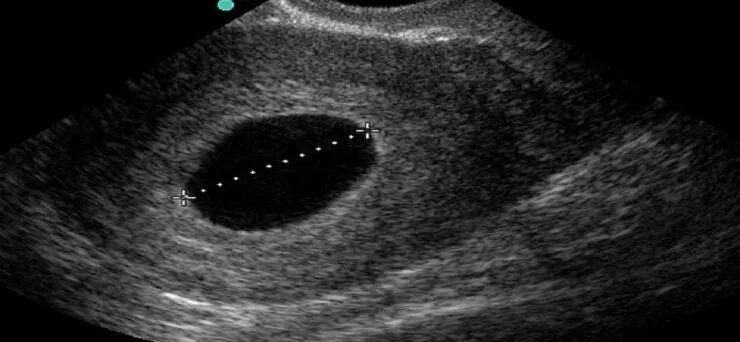

Почему может быть замершая беременность